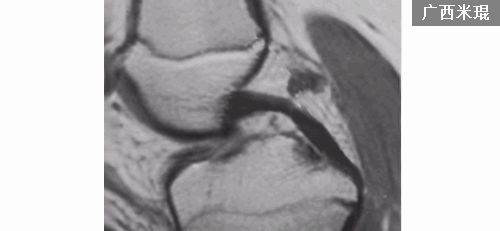

1.韧带实质部撕裂 (根据表现分为3级)

Grade1:韧带内损伤,无长度改变。

Grade2:韧带内损伤并长度延长。

Grade3:完全性韧带撕裂。